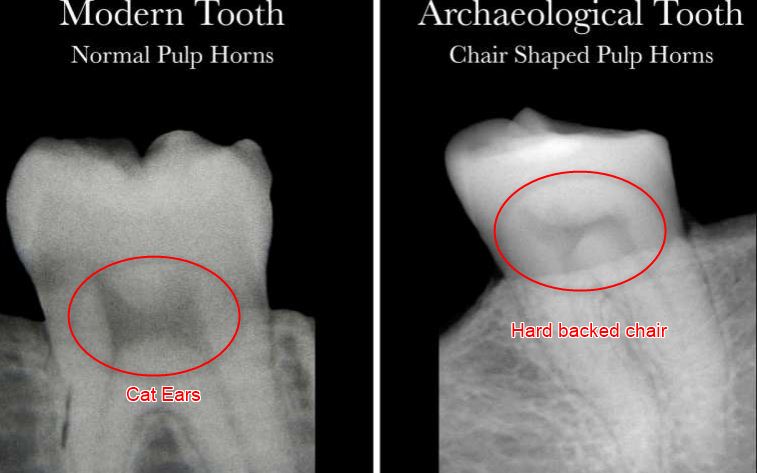

- “The pulp shape in a healthy person's tooth resembles an arch topped by two cat ears, while the pulp shape of a person who has had a severe deficiency of Vitamin D is asymmetrical and constricted, and typically looks like the profile of a hard-backed chair.”

This study investigates morphological changes in pulp chambers of living and archaeological individuals with past vitamin D deficiency. Living individuals (n = 29), four with detailed medical and dental records and three groups of archaeological individuals (n = 25) were radiographed; selected individuals were further evaluated histologically for the presence of incremental interglobular dentin (IIGD), indicative of deficiency (28 living; 17 archaeological). Measurements of pulp horns/chambers from radiographs were conducted to quantify morphological observations. One group had clear skeletal evidence of rickets from St. Matthew, Quebec (n = 1) and St. Jacques, France (n = 4); a second group had slight skeletal indicators from Bastion des Ursulines, Quebec (n = 6); and a third group lacked both skeletal and radiological evidence of deficiency from St. Antoine (n = 6) and Pointe-aux-Trembles (n = 4). Results showed archaeological individuals with clear and slight skeletal evidence of past deficiency displayed constricted or chair shaped pulp horns. Living individuals with deficiency exhibited similar pulp chamber morphology. Radiographic pulp horn/chamber measurements corroborated morphological findings and significant differences were found in pulp horn/chamber measurements between those with and without deficiency. Results suggest that radiograph assessment of teeth can be used as a screening technique to elucidate patterns of deficiency and select individuals for microCT or histological assessment.